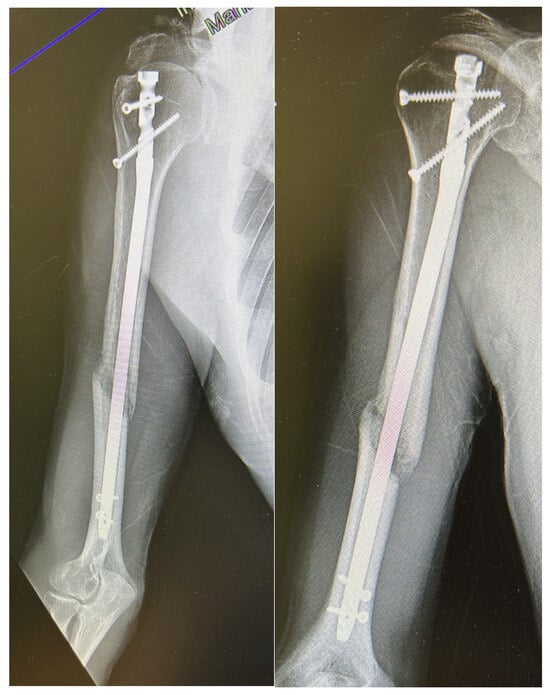

When complications were analyzed according to fracture location, radial nerve injuries were more frequent in distal-third fractures (5/42; 11.9%) compared with middle-third fractures (3/120; 2.5%) (p = 0.049), while no cases occurred in proximal-third fractures. Other complications, such as screw mobilization or delayed union, showed no clear association with fracture level. A representative case of atrophic nonunion observed nine months after antegrade intramedullary nailing is presented in Figure 1, illustrating the radiographic features of persistent fracture line and absent callus formation.

Figure 1.

Radiographic example of humeral shaft nonunion after antegrade intramedullary nailing. The images obtained 9 months postoperatively show a persistent fracture line with no cortical bridging or callus formation, consistent with atrophic nonunion.